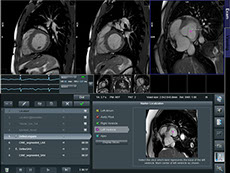

USAA ~ Safeway ~ Limited Brands ~ Macy's ~ Sears ~ Emporium ~ Nokia ~ Motorola ~ Samsung ~ LG ~ BlackBerry ~ HTC ~ Wal-Mart Stores ~ CVS ~ Best Buy ~ Rite Aid ~ Nike ~ GAP ~ J. C. Penney ~ Chevron ~ General Electric ~ AT&T ~ Hewlett-Packard ~ Bank of America Corp. ~ Citigroup ~ Berkshire Hathaway ~ International Business Machines ~ McKesson ~ Kaiser Permanente ~ Kaiser Hospitals ~ U.C.S.F ~ Stanford University School of Medicine/Medical Center ~ Sutter Healthcare ~ California Pacific Medical Center ~ San Francisco General Hospital And Medical Center ~ San Francisco VA Medical Center ~ U.S. Department of Transportation ~ U.S. Department of Homeland Security ~ Exar ~ Boeing ~ AIS ~ Siemens ~ Kaiser People Solutions ~ Cardinal Health ~ Procter & Gamble ~ UnitedHealth Group ~ Kroger ~ Marathon Oil ~ Costco Wholesale ~ Home Depot ~ Target ~ Johnson & Johnson ~ Morgan Stanley ~ State Farm Insurance ~ Dell ~ Boeing ~ Microsoft ~ Walgreen ~ United Technologies ~ Dow Chemical ~ MetLife ~ Wells Fargo ~ United Parcel Service ~ Caterpillar ~ Lowe's ~ Sears Holdings ~ Cisco Systems ~ Johnson Controls ~ FedEx ~ Intel ~ Sysco ~ Comcast ~ Coca-Cola ~ American Express ~ Aetna ~ Motorola ~ Allstate ~ Prudential Financial ~ Tyson Foods ~ Staples ~ Delta Air Lines ~ City and County of Sacramento ~ City and County of San Francisco ~ City and County Oakland ~ San Jose International Airport ~ JFK International Airport